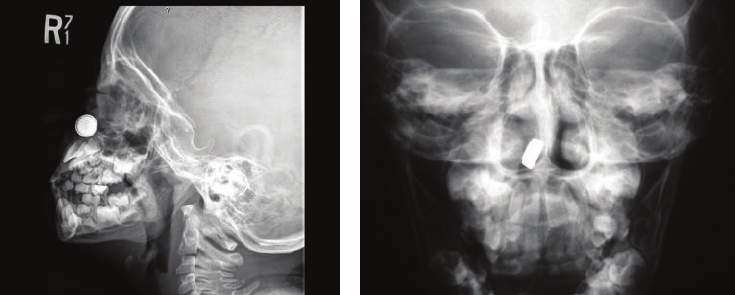

X光機下拍到的各種異物

耳朵

・無線耳機

・寶石

・被小朋友塞入的細長玩具

・襯衫上的鈕扣或其他硬物

・岩鹽

・莓果

・為了挖耳屎反而卡進去的挖耳棒或鉗子

・體溫計

・珍珠

・附在飲料上的吸管

・微小芯片

・裝飾貝殼

・梳子斷掉的一小段尖端物

・果凍或凝膠

・塑膠蜘蛛

・聖誕節裝飾物

鼻子

・磁鐵

・小型的貼紙

・鈕扣般大小的電池

・粉筆

・飛進鼻子裡的蟲

・糖果包裝紙

・裝飾品眼睛

・驅蟲球

・葵花籽